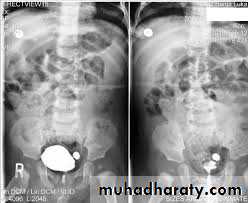

70- 80 % are calcified and show varying densities on plain film

The larger stone assume the shape of the PCS staghorn calculus

Plain film exam of the urinary tract ( KUB) is more sensitive than US for detecting opaque renal and ureteric stone .Plain film is essential to be used as a preliminary film before injection of the contrast in IVU and should be examined carefully because even a large stone can be hidden within the opacified collecting system once contrast medium has been given.

Most renal calculi of more than 5 mm are usually seen at US but smaller size calculi may be missed. Stones regardless of their consistency produce intense echoes and cast acoustic shadows.

Stones in the ureters cannot be excluded by US , so IVU or CT is indicated

Stones in the VUJ and bladder are well demonstrated by USCT when performed without contrast is sensitive for detection of all types of stones